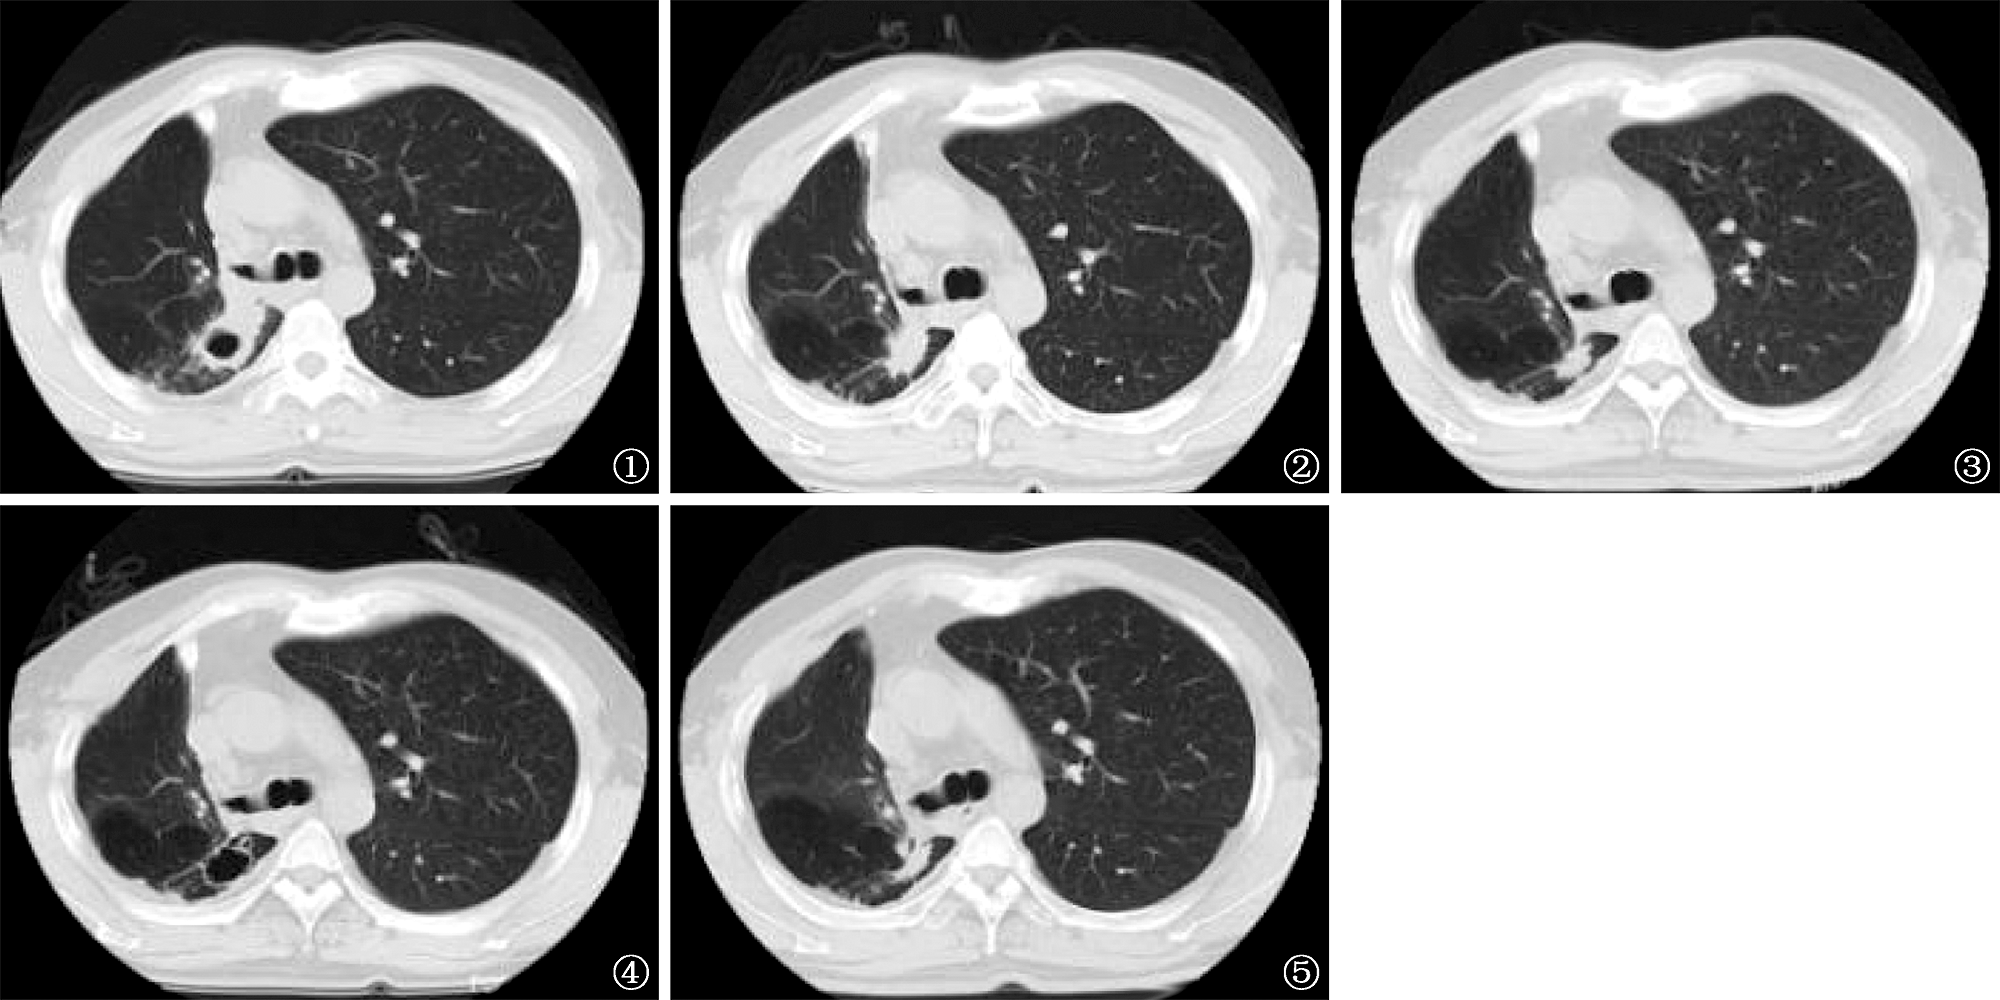

| 图1~5 患者,男性,准广泛耐药肺结核。图1为治疗前患者胸部CT检查图像,可见右肺空洞影(2022年4月)。图2为治疗3个月后胸部CT复查图像,可见右肺病变空洞较前明显缩小,部分空洞闭合(2022年8月)。图3为治疗12个月后胸部CT复查图像,可见右肺病变空洞进一步缩小(2023年5月)。图5为治疗19个月后胸部CT复查图像,可见右肺病变遗留小的薄壁空洞,基本为净化空洞(2023年12月)。图5为治疗24个月后胸部CT复查图像,可见右肺病变空洞基本闭合(2024年6月) |